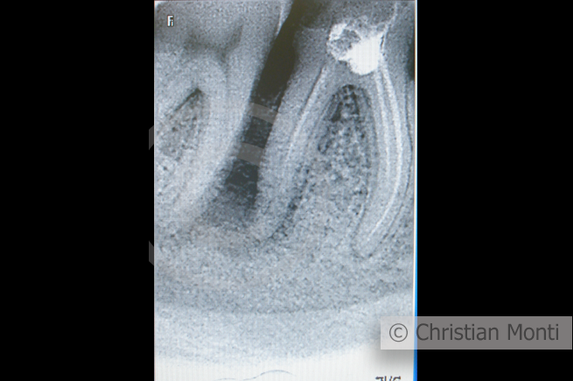

EDENTULIA SINGOLA

Impianto dilazionato in sostituzione di un molare inferiore